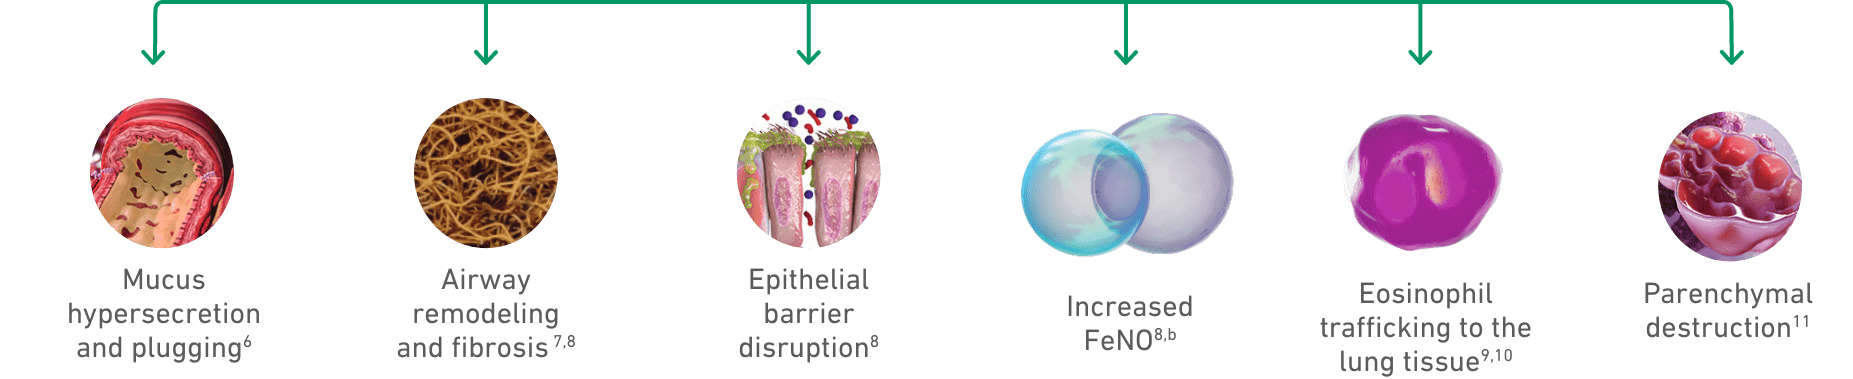

Mucus hypersecretion

Airway remodeling

and fibrosis7,8

Epithelial barrier

disruption8

Increased

FeNO8,b

Eosinophil

trafficking to the

lung tissues9,10

Parenchymal destruction11